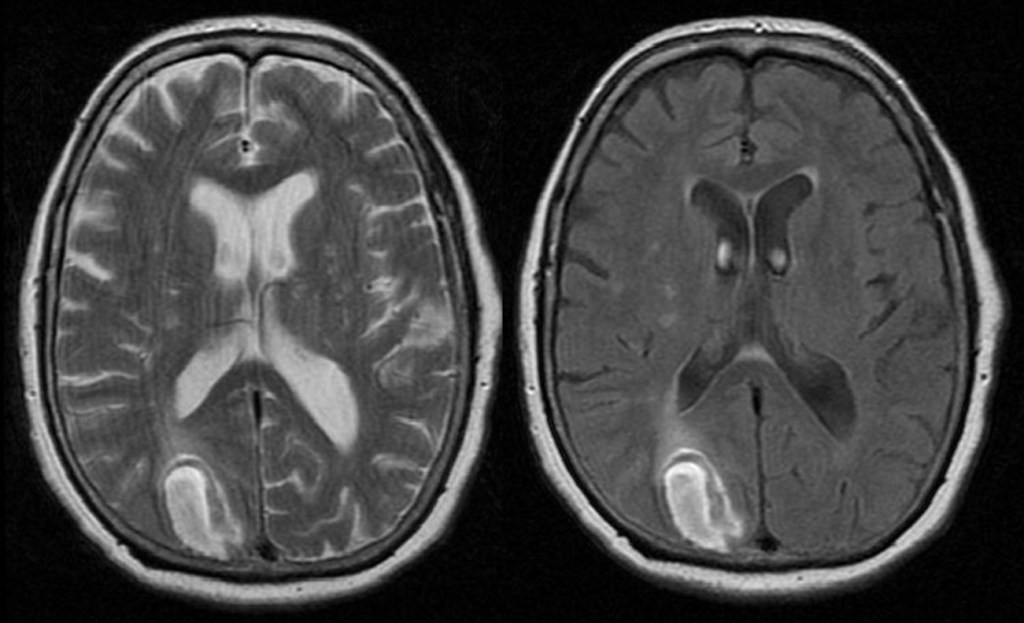

There’s no exact known number of diagnoses because many try to hide their symptoms out of embarrassment or don’t seek treatment. Symptoms vary but commonly include a desire to be disabled or live without that body part, discomfort with that body part, isolation, behaving like you have a disability, and sometimes self-harm. It’s hard to know exactly what causes BIID, but doctors theorize structural abnormalities in the brain that regulate bodily perception, possibly in the somatosensory cortex, parietal lobe, and insula.

The short answer is no. Mental illness is not a disease or virus that can be erased. In the 1940s and 50s, treatments included cutting the frontal lobe or locking someone in a padded room, but psychology has come a long way since then. Many people still treat mental illness as taboo or believe it doesn’t exist. In the syndromes listed, there are often changes in brain matter. You can go to therapy and take antipsychotics, but it won’t just disappear.